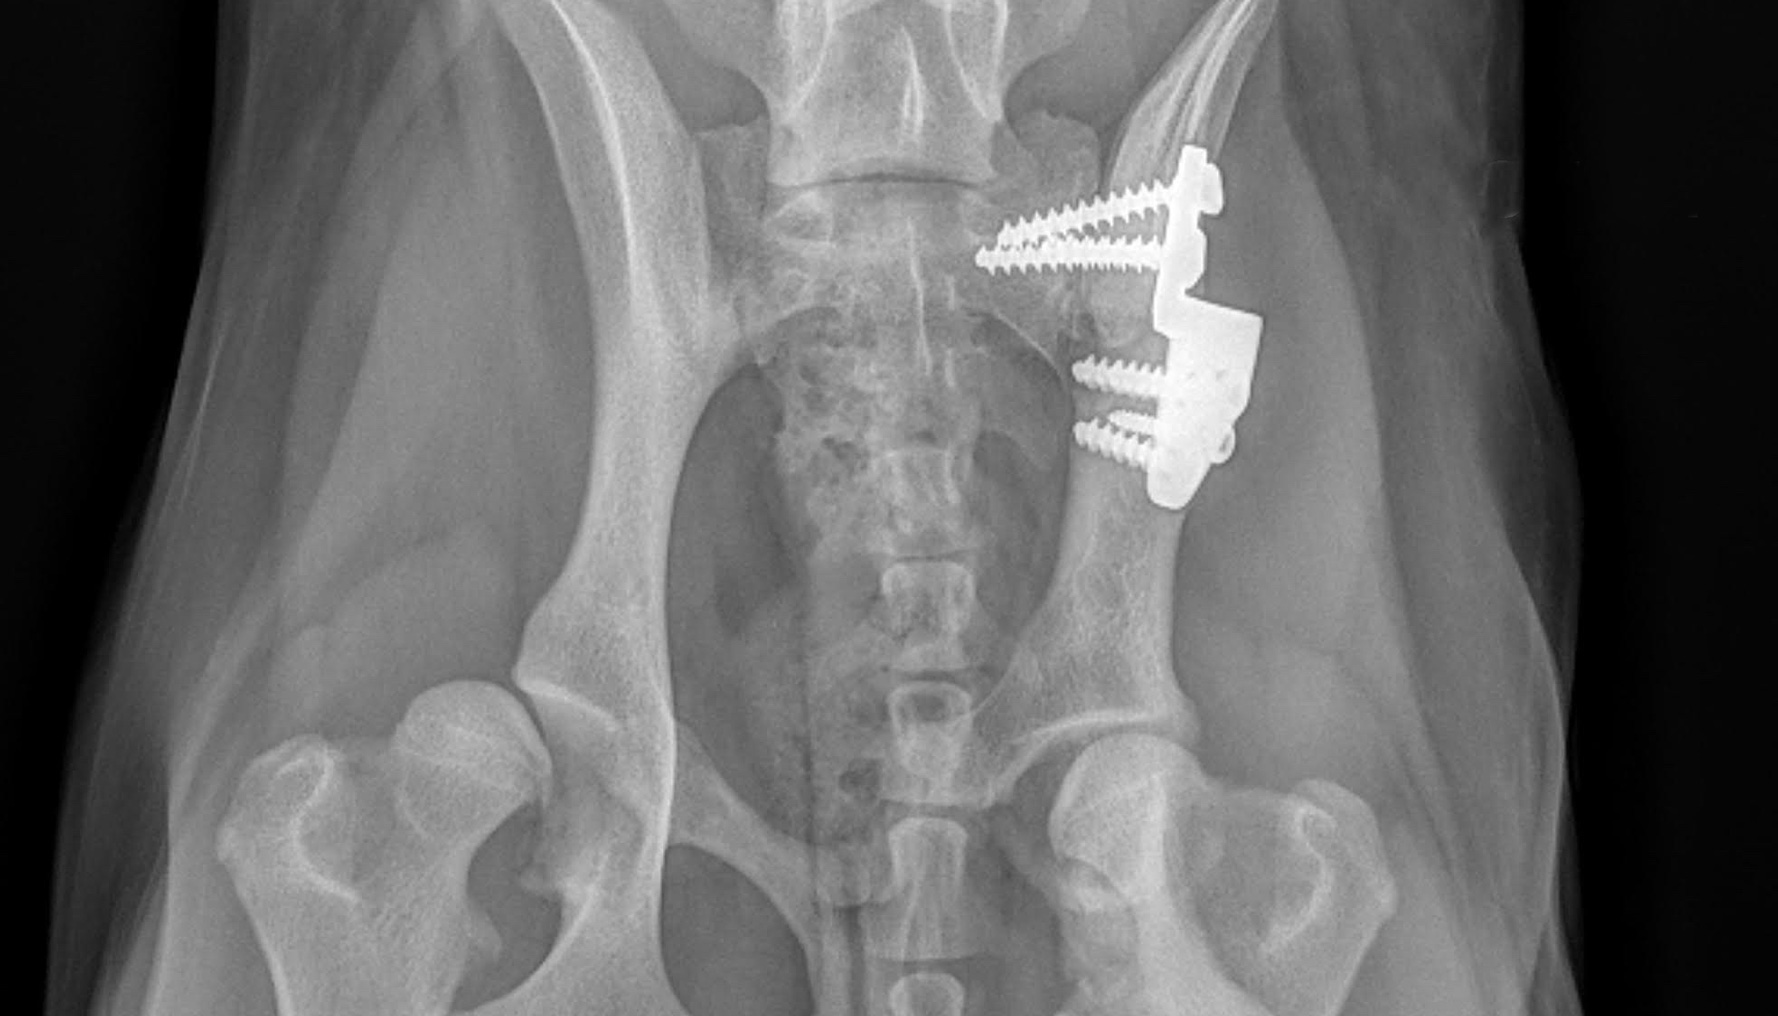

Orthopedic surgery is any surgery that involves your dog's skeletal system and the bones, joints, tendons, muscles, ligaments, and cartilage associated with it.